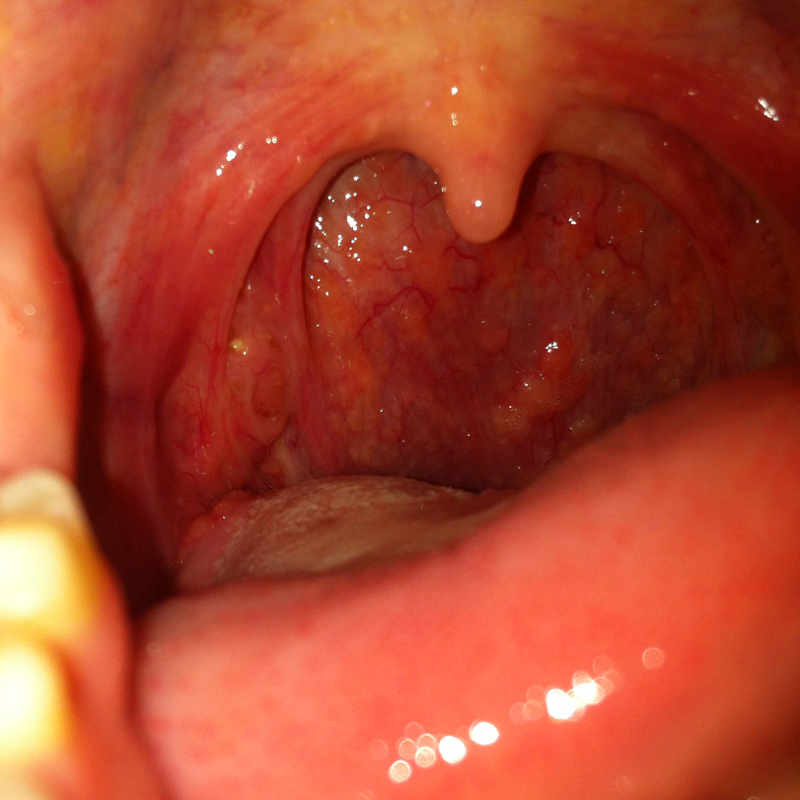

Eitrige Mandelentzündung oder doch mehr (siehe Bild)? (Bilder, krank